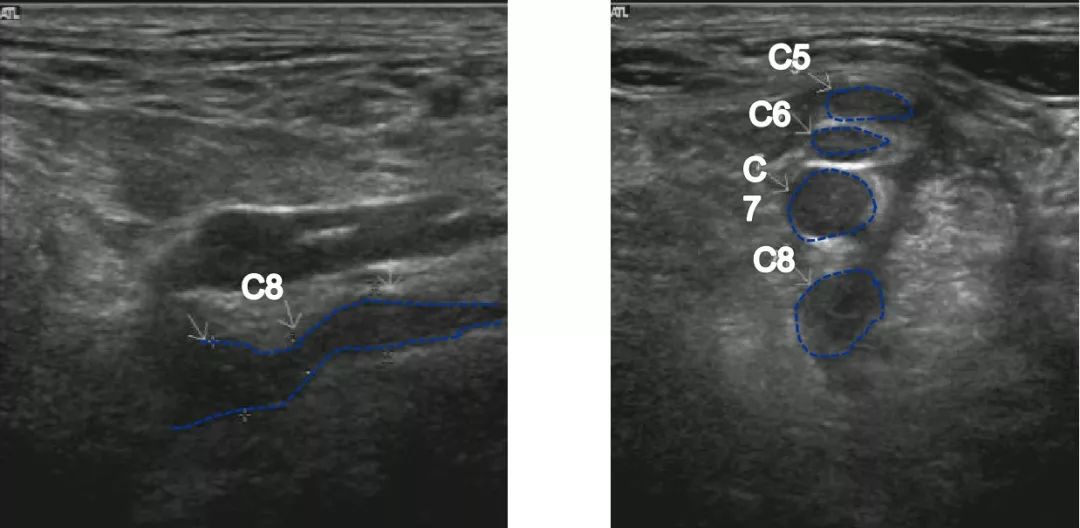

臂丛神经超声图

臂丛神经超声图,腋路臂丛神经超声图片